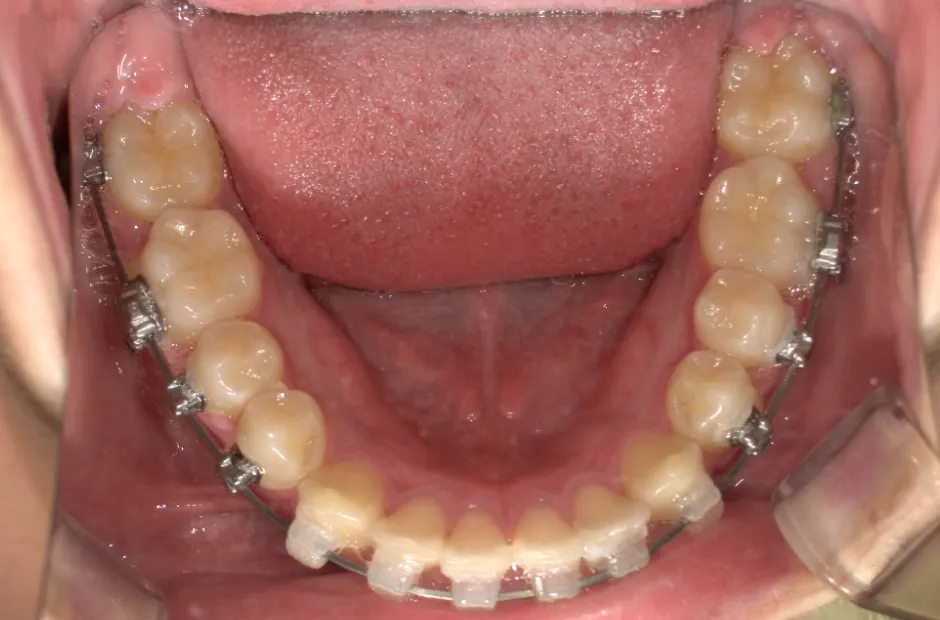

リンガルアーチ

| 診断名・主訴 | 反対咬合 |

|---|---|

| 年齢・性別 | 14歳・女性 |

| 治療期間・回数 | 2年6か月 |

| 治療に用いた主な装置 | リンガル |

| 抜歯部位 | 上顎5,5 下顎4,4 |

| 治療費 | 100万円(税抜) |

| リスク・副作用 | 装置による違和感・疼痛・歯肉退縮・歯根吸収・虫歯のリスクなど |

治療中